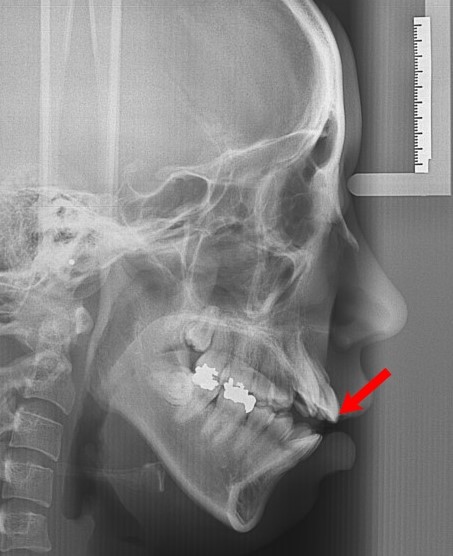

위 사진을 보시면 이 환자의 경우 덧니와 돌출입까지

동시에 나타난 것을 알 수 있는데요

덧니를 제 자리로 옮기고 돌출된 입도 넣어야 했기 때문에

발치교정을 결정하고 교정을 시행했습니다. 아래 사진은 교정 후 사진입니다

교정기간 : 2년 10개월

명동점에서 치료